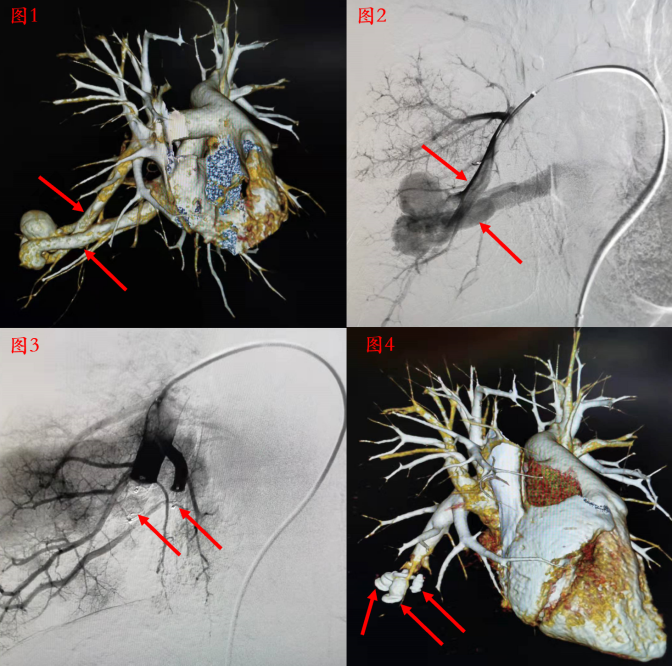

Case 2 封堵器封堵肺动静脉瘘

图1,CTA显示右肺动静脉瘘,上方箭头为右肺动脉流入道,下方箭头为肺静脉流出道;图2 造影显示右肺动静脉瘘;图3,封堵器封堵后造影显示病变血管封堵良好,动静脉瘘未再显影;图4,术后随访CT,箭头所指为3枚封堵器。